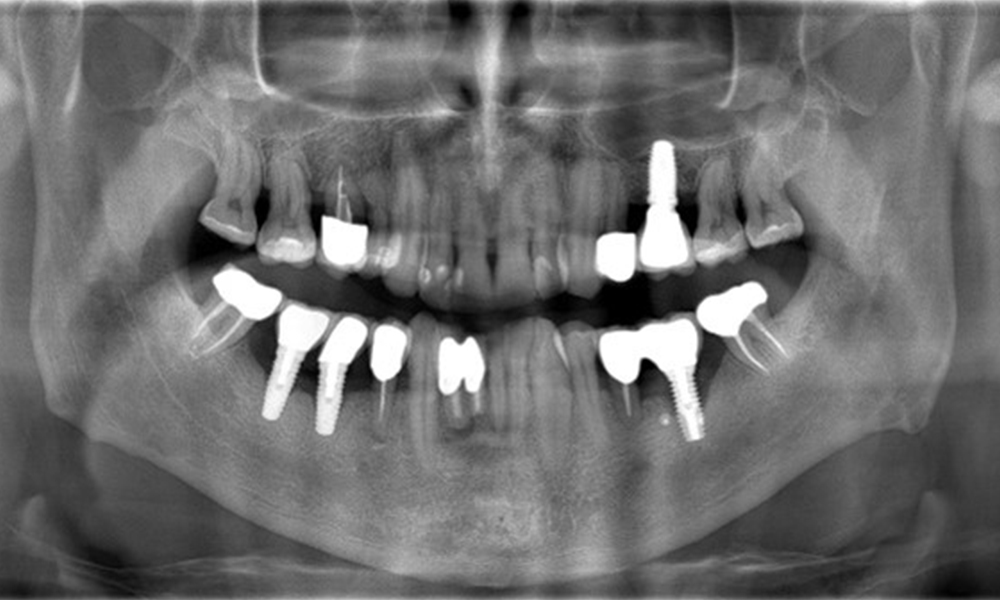

A 52-year-old patient presents at a preventive care session. The patient has no systemic disease and is not taking any medication. He has had various dental treatments and also has two active carious lesions. In addition, the patient has four implants (2nd, 3rd and 4th quadrants). He is revealed to have early periodontal disease (stage IV, grade B). His periodontal condition is stable; a probing depth of Probing depths (ST) of 5 mm is only evident at the implant in region 36. Gingivitis is also identified.

The X-ray images show the progression of bone loss.

The X-ray images show the progression of bone loss. OPG from 29.06.2020 (left) and OPG from 26.02.2024 (right).

OPG: 26/02/2024 Dental X-ray: 18/01/2024